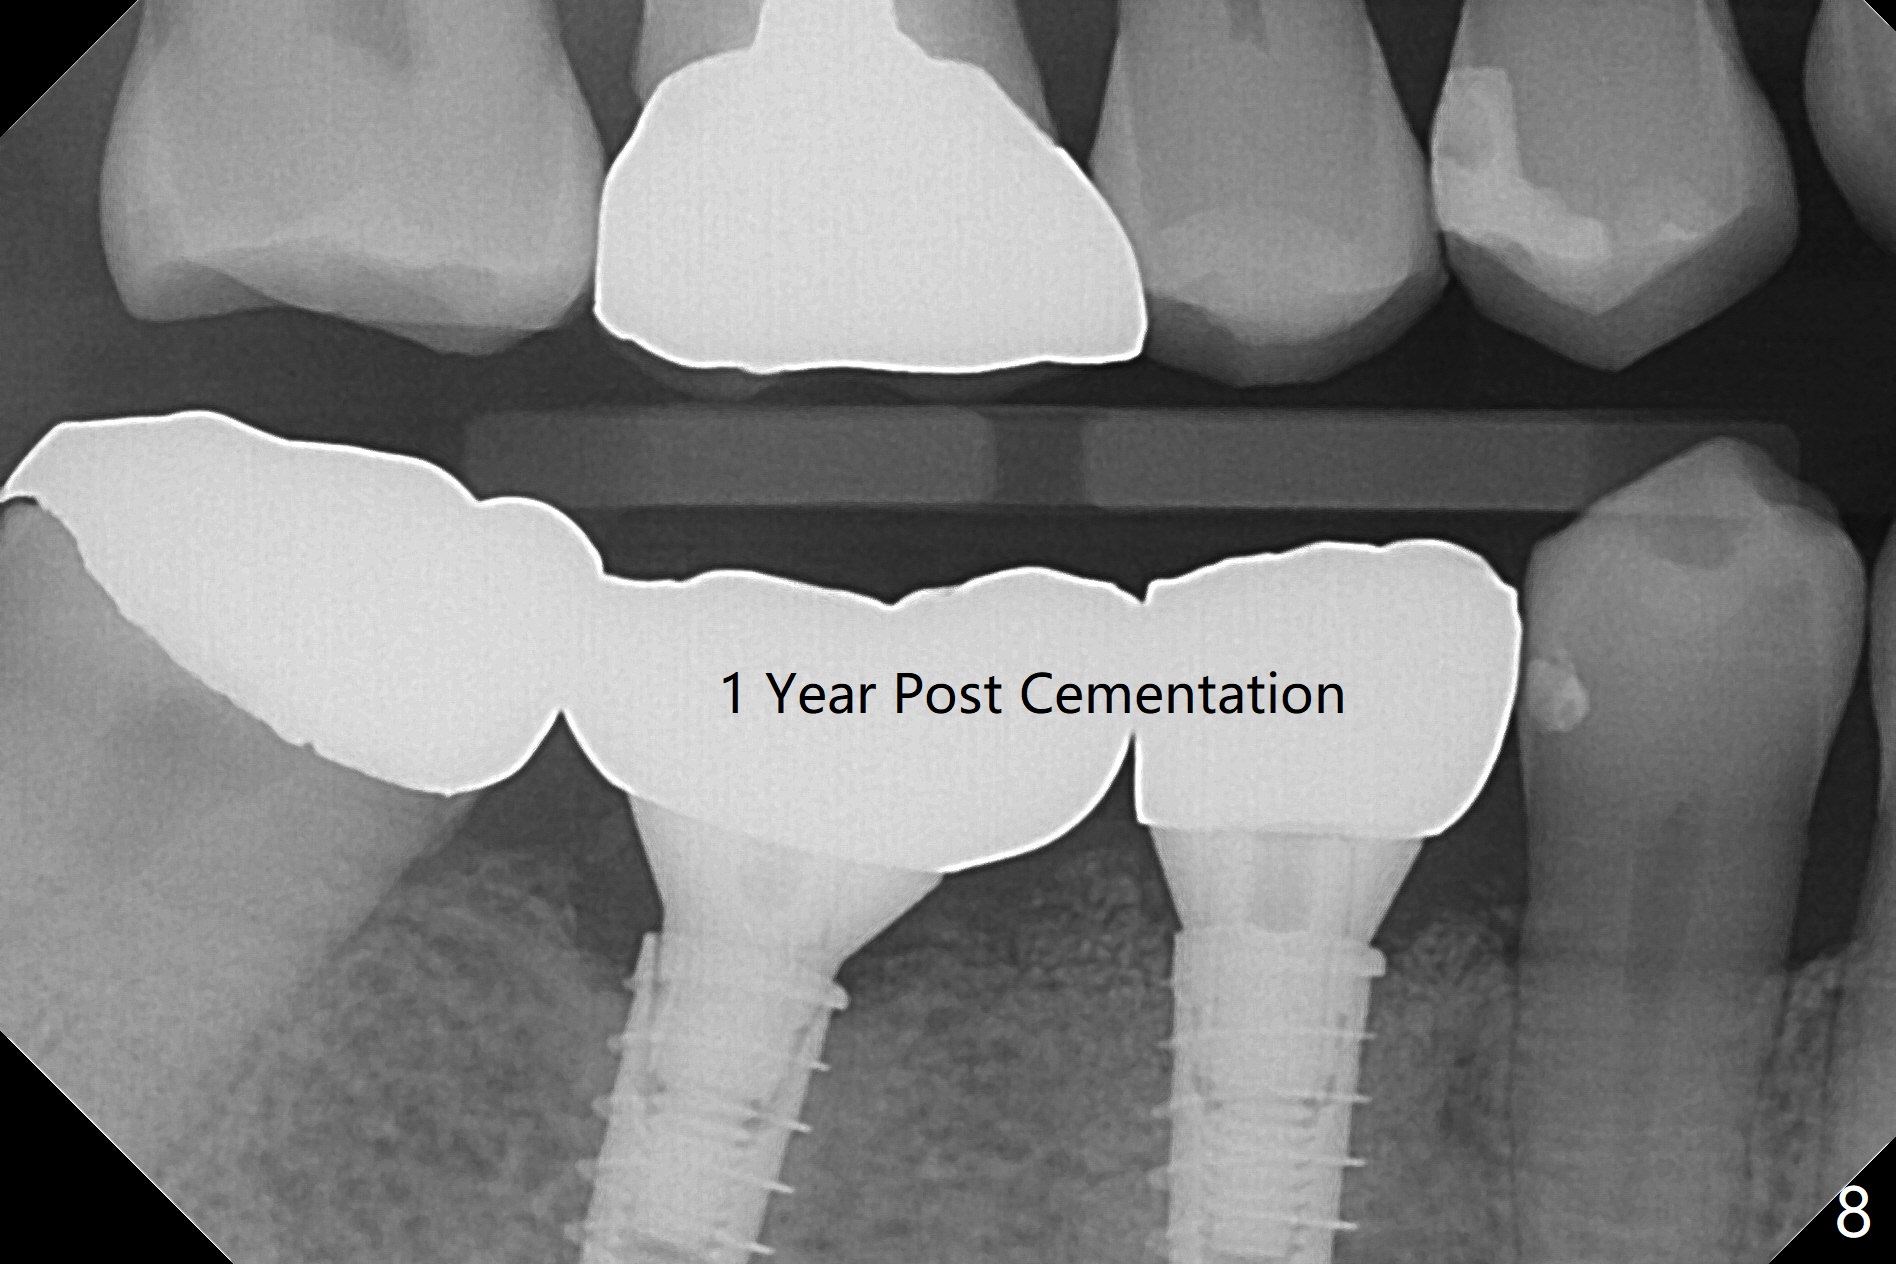

After incision, the ridge at #29 and 30 is found ~ 5 mm wide buccolingually. To place a 4x11 mm IBS implant at #30, the ridge is expanded using BEB technique (bone expansion and bending, Fig.1). It appears that the initial osteotomy at #29 is mesial (Fig.1 yellow dashed line: the distal surface of the root of the tooth #28). After moving the osteotomy distal, the final implant position at #29 (4x11 mm) is within normal limit (Fig.2). The bone at #29 seems to be not so dense that bending (using 1.6 mm drill) is not necessary (using Magic Split and Magic Expanders 3 and 3.8 mm). Later the implant at #30 (4x11 mm) is placed deeper (Fig.3). After placing bone graft around the implants/abutments and suturing, the ridge looks wider with apparent formation of the gingival bands around the abutments (Fig.4 *). Three months and a half postop, bone loss is minimal (Fig.5) and gingival bands forms around the abutments (Fig.6). Fig.7 is taken 1 month post cementation (panoramic X-ray). The patient chews normally 1 year (Fig.8) and nearly 2 years (Fig.9,10) post cementation. The crown at #31 needs recementation 2 years 7 months post #30 cementation; the incomplete seating of the abutment was noted for the first time (Fig.11). Five months later the patient is going to be retired and wants to travel abroad. After approval, the access hole was reopened; articulating paper shows under occlusion of the crown (Fig.12). Since the gap between the abutment and the implant is large, the abutment/crown complex seems to be necessary to be turned (Fig.13 curved arrow). The proximal surfaces of the crown need to be trimmed (straight lines). After turning, the crown sits down with screw tightening; the patient feels pain from the gingival cuff (Fig.14). After turning, the abutment appears to be completely seated (Fig.15). In fact the mesial and distal surfaces of the crown should have clearance from the neighboring teeth (Fig.14) so that pick-up impression is able to hold the crown/abutment complex securely (Fig.16: *). The crown is separated from the abutment after crown repair. They are seated together (loose connection) using the crown as a guide to seat the abutment. BW is taken without the crown. It appears that the abutment remains seated completely (Fig.17). The apical space is equal between #29 and 30 (Fig.17, as compared to Fig.5).